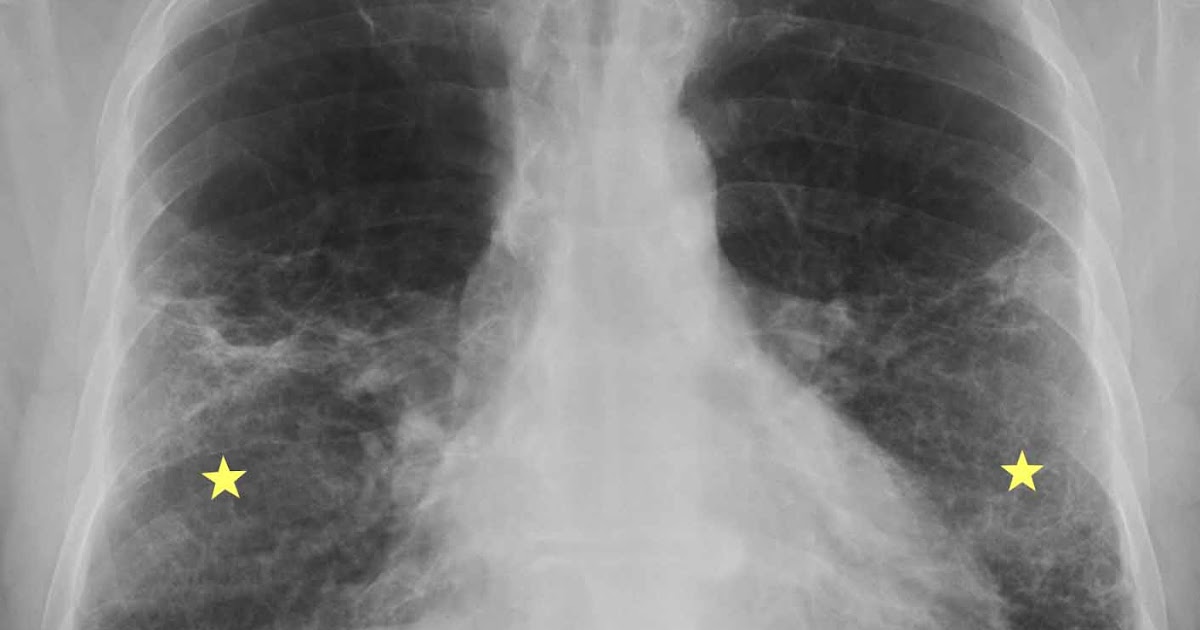

RiT radiology Acute Exacerbation of Idiopathic Pulmonary Fibrosis Ild Exacerbation Radiology — these exacerbations are characterized by increased dyspnea and cough and decreased oxygen saturation. Katy black, md division of pulmonary and critical care medicine massachusetts. — the aim of this review is to provide a summary of the definition,. — acute exacerbations of ild. Ild Exacerbation Radiology.